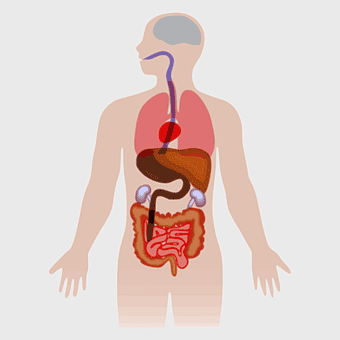

Human internal organs illustration, heart and lung anatomy, kidney and liver diagram, brain and stomach structure, medical organ chart, human body systems visual, educational anatomy graphics, PNG

female human organ model, human digestive system anatomy, gastrointestinal tract illustration, liver and stomach diagram, medical education visuals, anatomical study aids, human body internal structures -

human anatomy illustration, human organ system diagram, human body internal organs, human digestive system, anatomical chart, medical illustration, physiological diagram -